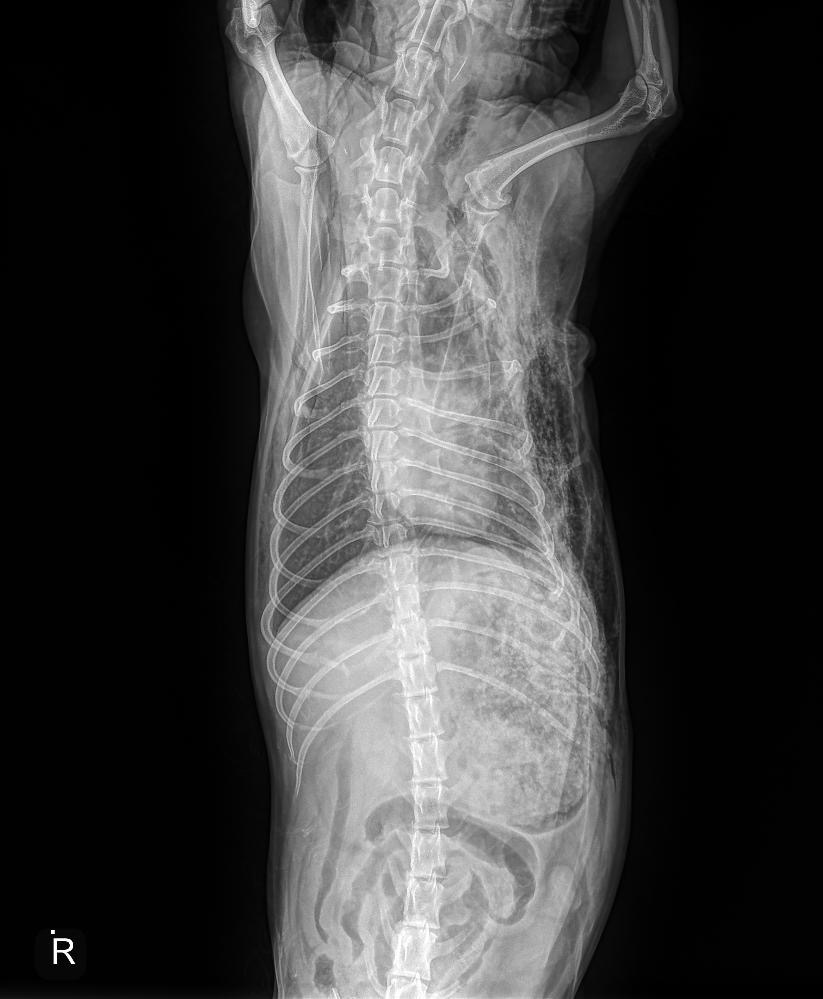

Over this past weekend, I came home from dinner to find my Toby covered in blood at his stomach and legs, and a trail of his blood coming from the backyard. There have been coyote sightings in our area, but my family and I never thought much of it at the time. I frantically took him to urgent care for animals, and they confirmed that multiple coyotes got to my Toby, biting his stomach, chest, neck, head, butt, and legs. He walked away with several bite marks, 3-4 broken ribs, a punctured chest, and in need of a possible stomach surgery. The doctors gave me a 60% survival rate as he lost a lot of blood and his heart rate was extremely high from the attack. Luckily, Toby is a strong soldier and beat the odds. He now goes to his daytime clinic for further treatment and is recovering slowly.